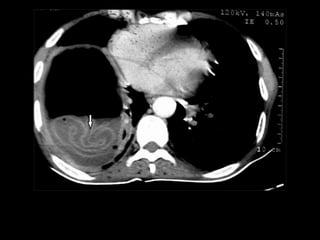

Cannon Ball Metastasis